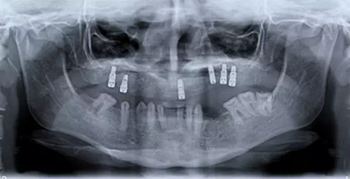

圖 2. 曲面斷層片(術(shù)前、拔牙后、種牙后)